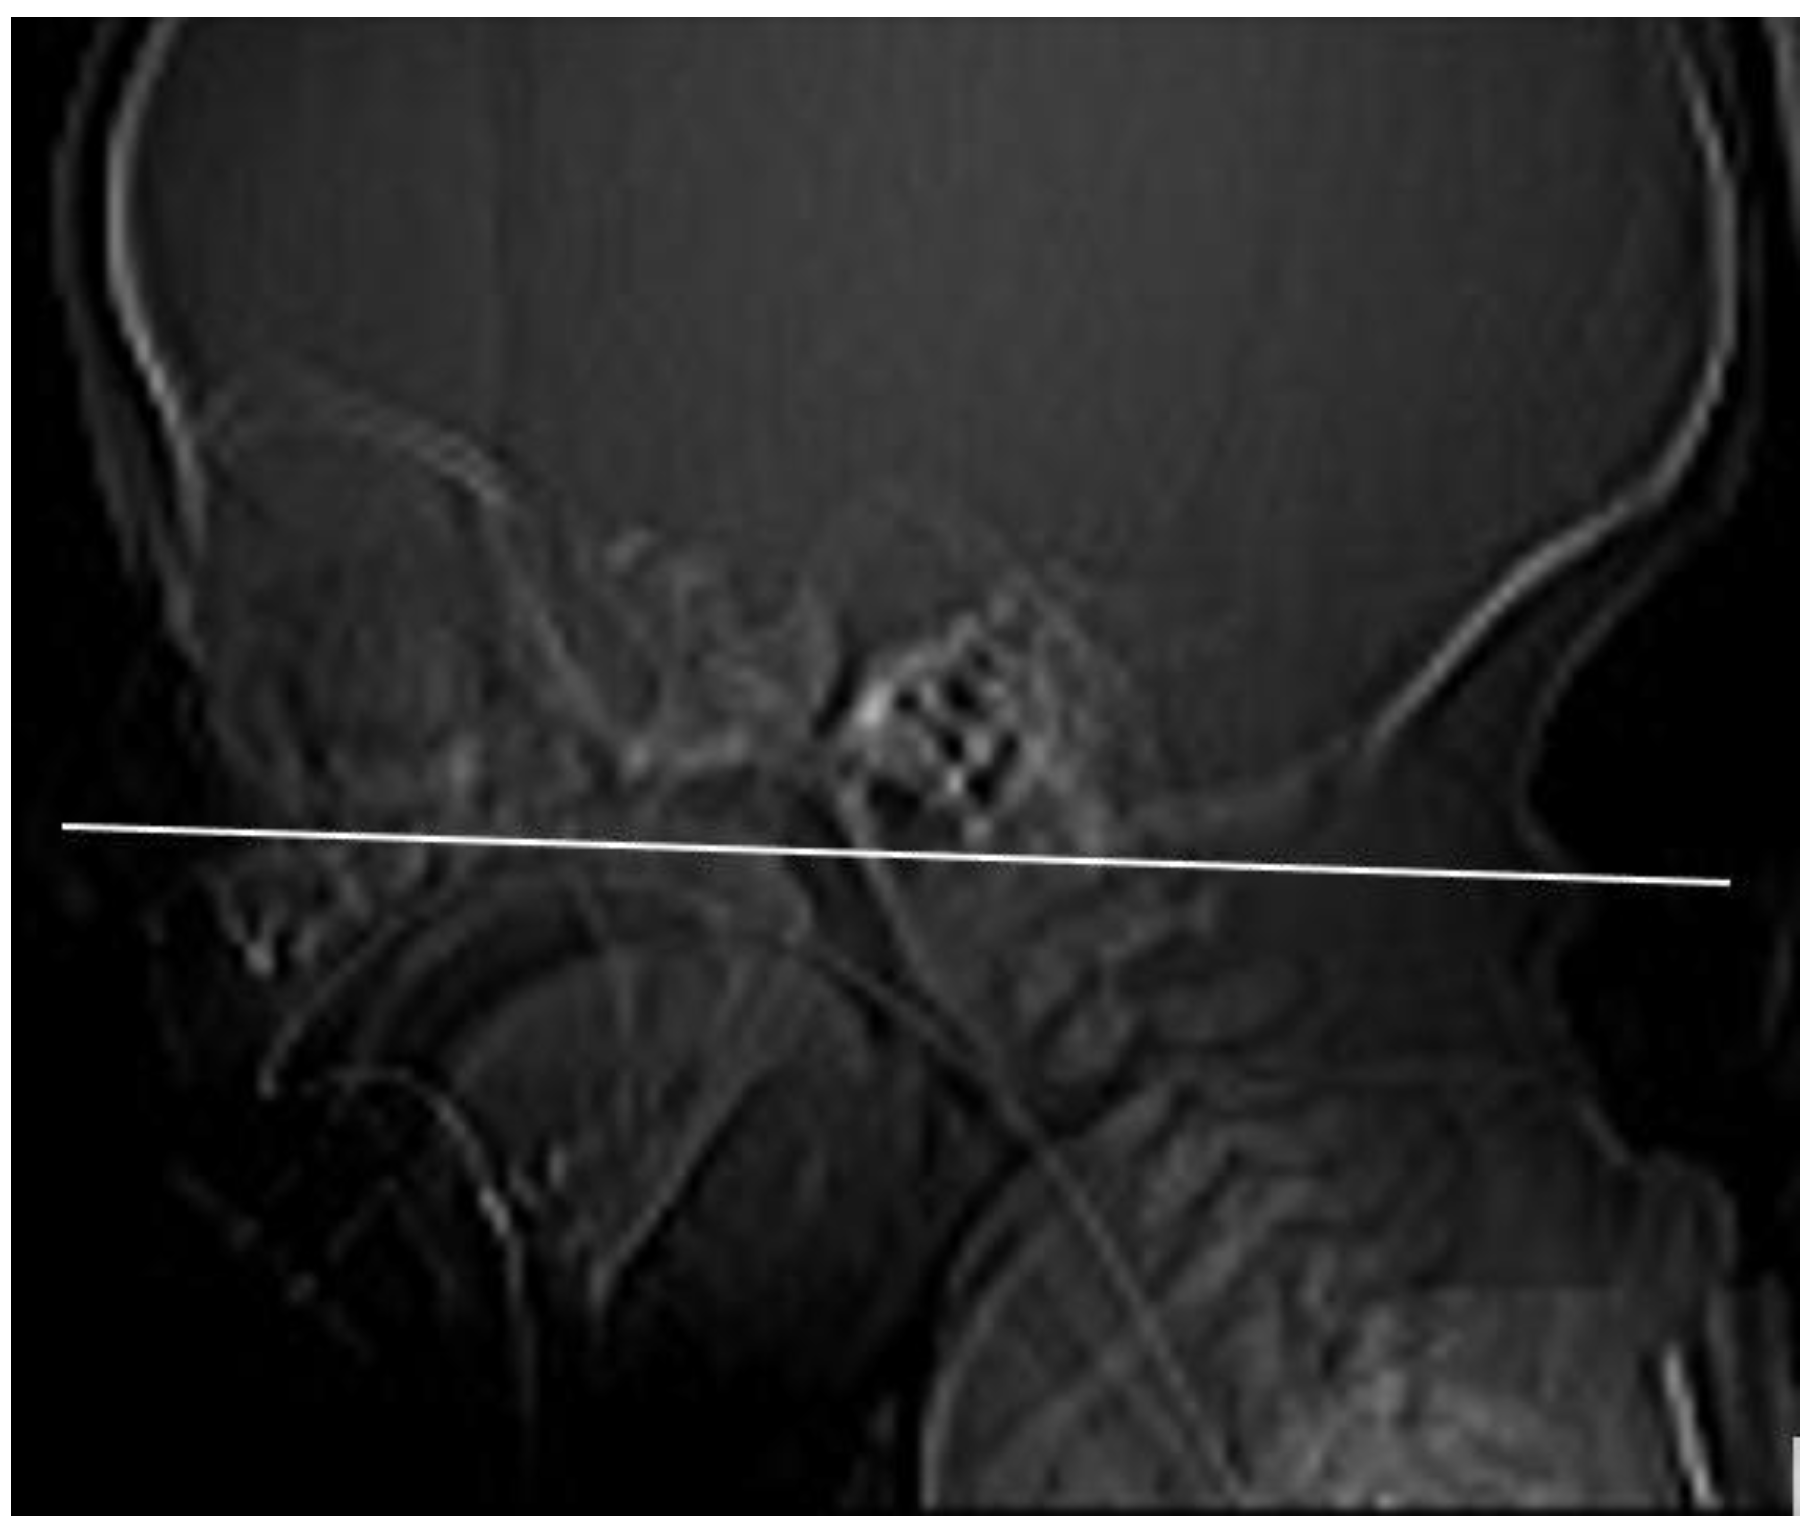

We have evaluated the nasal cavity CT imaging of 24 pediatric patients diagnosed with ICD-10: Q30.0 choanal atresia examined at the Department of Pediatric Otorhinolaryngology of the Medical Faculty of the Comenius University and the National Institute of Children’s Diseases in Bratislava (Slovakia). We have recorded the sex of patients, the presence of syndromes, their age at the time of the nasal cavity CT examination, and the types of atresia (congenital–acquired, unilateral–bilateral). In the case of the unilateral atresia, we have examined which half of the nasal cavity was affected. We determined the character of the atretic plate (membranous, bone-membranous, and bone types) and their locations (unilateral, bilateral) [4]. Using the method of Slovis et al. (1985) [10], a CT section paralleling the posterior hard palate at the level of the pterygoid plates was obtained in all children (Figure 1). The sections were 0.5 to 1 mm thick. The TomoCon PACS system was used for CT scanning. The measurements were obtained by one examiner with Tomocon Viewer application measuring tools.

Figure 1.

The measurement plane: CT section paralleling the posterior hard palate at the level of the pterygoid plates.